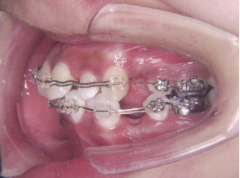

装置装着前

装置装着後